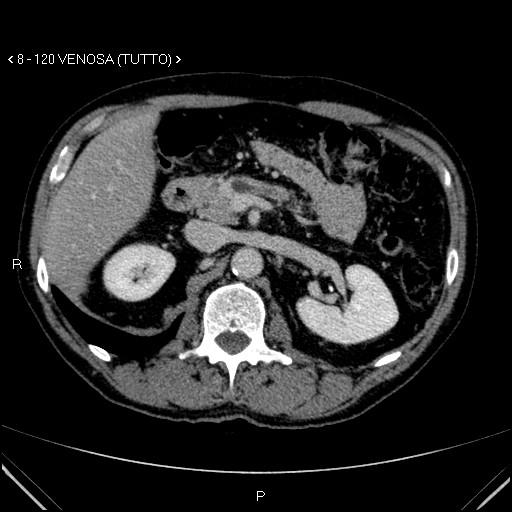

Aspetti TC: piccolo nodulo istmico ipervascolarizzato in fase pancreatica

image